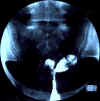

| Utérus cloisonné avec un grand septum, large dans sa partie fundique et long, s'étendant jusqu'à l'isthme utérin. Ce septum mesure environ 5 cm de longueur pour 5 mm d'épaisseur. L'isthme s'en trouve élargi, mesurant 11 mm de face. Les deux hémicavités secondaires sont de petite taille, mais avec des contours lisses et réguliers, sans aucune image d'addition ni de soustraction. L'angle entre les deux hémicavités est d'environ 600, confirmant le diagnostic d'utérus cloisonné.

Les deux trompes sont perméables, légère stagnation du contraste dans les deux ampoules, plus marquée à gauche.

Conclusion:

Utérus cloisonné avec un septum de grande taille s'étendant jusqu'au niveau de l'isthmeTrompes perméables, stagnation de contraste dans les ampoules, plus marquée du côté gauche |    |